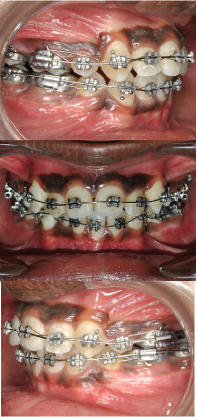

The case was treated using “Hybrid Segmental Mechanics” with extraction of all four 1st premolars with initial segmental retraction of maxillary canines and mandibular right canine using 0.017x0.025" TMA (Titanium, Molybdenum, Aluminum), ‘T-loop’ retraction spring [1,2] [Table/Fig-4a&b]. After segmented retraction of canine, leveling and alignment was carried out using continuous arch sliding mechanics using 0.016" Ni-Ti [Table/Fig-5a-c] and 0.019x0.025" Ni-Ti [Table/Fig-6a-c]. Residual Space closure was achieved using class II elastics [Table/Fig-7a&b]. In mandibular arch, right first molar was protracted to attain class I molar relationship. Finishing and detailing was carried out after closing all spaces. Most of the treatment objectives were met with the treatment, with good intraoral and facial results [Table/Fig-8a-c,9a-e,10a&b,11]. Pretreatment & post-treatment superimposition showed significant dento-alveolar change and good vertical control [Table/Fig-12a&b].

After initial segmental mechanics, continuous arch-wire sliding mechanics with 0.016" Ni-Ti in upper and lower arch.

Continuous arch-wire sliding mechanics with 0.019"x 0.025" Ni-Ti in upper and lower arch.